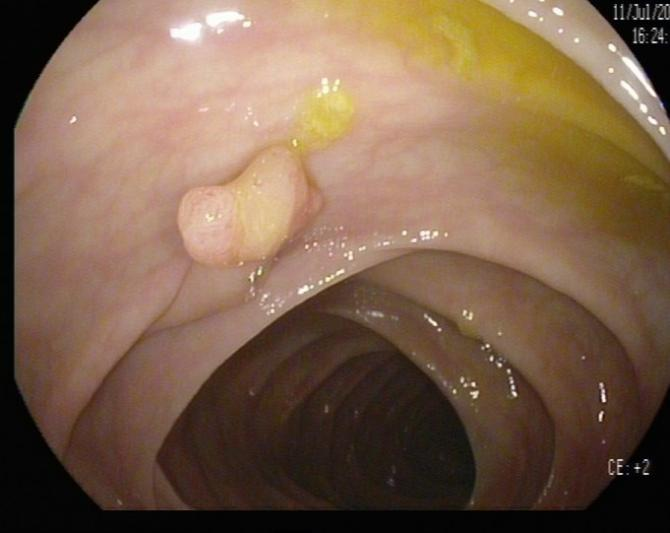

(3)邓先生(54岁,乙状结肠息肉,图3)

肠镜一照,息肉现形!形态各异的大肠息肉,离癌有多远?(图3)

图3

病理诊断:(乙状结肠)管状腺瘤。

解读:这是最常见的腺瘤类型。若未发现高级别瘤变或癌变,属于相对早期的癌前病变。但放任不管,其癌变风险随时间推移而增加。距离癌:潜在风险,癌前病变早期。